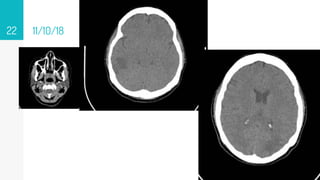

11/10/18

22

12/09/18

▹ 12/09/18

• #83 12 09 18 Area hipodensa en sustancia blaca subcotical en región frontal 20x17 mm 23-32 ud Onfl con dedema perilesional 11 10 18 imagen hipodensa digitiforme en rango 42- 47 Unid Onfil cortico-subcortical en lóbulo frontal derecho, 17.25 und Onfil lóbulo parietan e imagen en región occipital sin aumento de la amplitud de los ventrículos RM 30 10 18 se observan imágenes algunas hipodensas en secuencias T1, otras de señal intermedia muy heterogéneas, hipointensas en secuencias Flair y T2 con realce importante algunas en forma nodular, otras en forma periférica posterior a la administración de gadolinio, las de la región temporal derecha y occipital ipsilateral, con edema perilesional, mucho más importante en la de la región occipital, que debe correlacionarse con antecedente clínico reciente. En el Centro semioval en el lado izquierdo se observan pequeñas imágenes puntiformes hiperintensas en secuencias Flair y T2 pueden corresponder a lesiones vasculares isquémicas de pequeños vasos